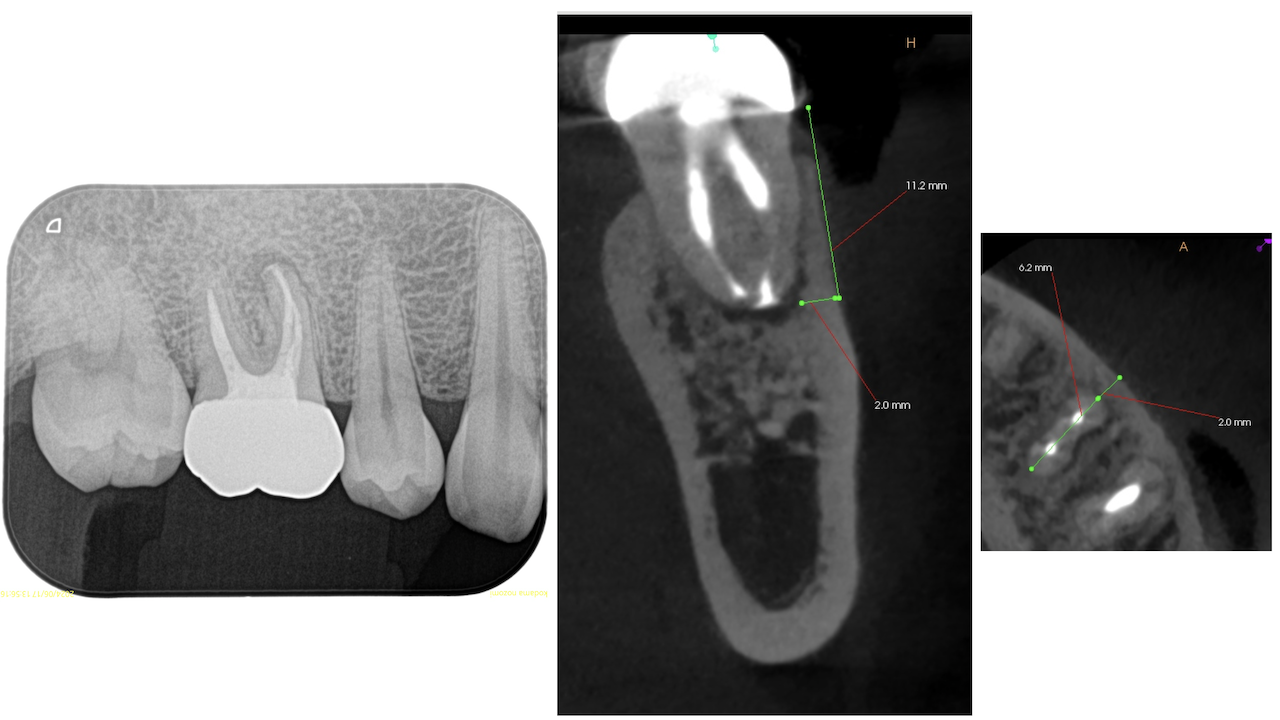

Pre-op Endo(2024.6.17)

#19 Cold N/A, Perc.(+), BT(+), Palp.(-), Perio Probe(WNL), Mobility(WNL)

臨床症状の原因は#19の近心根の根尖病変だろう。

再根管治療に見込みはないため、Apicoectomyなのだが

当該部位を2mm Osteotomyすると#19 MのApexが発見できそこを3mm切断するには頬舌径が6.2mm必要である。

Pulp Dx: Previously treated

Periapical Dx: Symptomatic apical periodontitis

Recommended Tx: M Apicoectomy